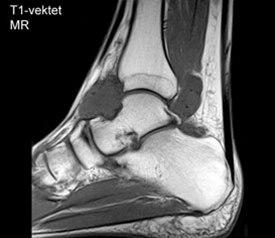

Røntgenbilde vil et stykke ut i forløpet som regel gi diagnosen og viser mange forkalkede biter inne i leddet. Det kan også foreligge slitasjeforandringer. Tidlig i sykdomsforløpet kan det mangle forkalkninger. MR er den beste undersøkelsen og kan være nødvendig ved manglende funn ved andre undersøkelser eller før en eventuell operasjon.